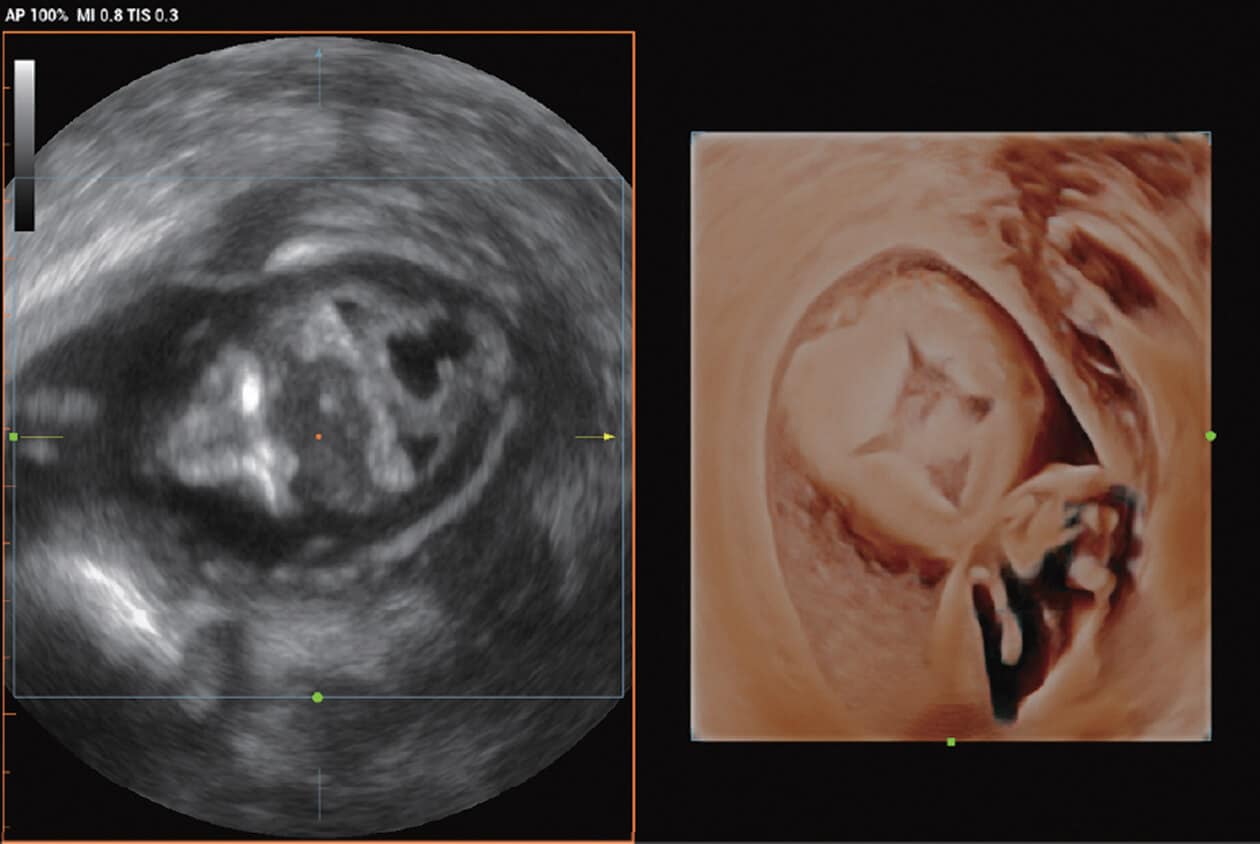

Powered by Mindray’s revolutionary ZONE Sonography (R) Technology+, the Imagyn I9 System boasts advanced ultrasound capabilities and leverages AI-inechanged technologies. The Imagyn I9 starts the process using auto clinical scenario identification, and uses automation at every point, from imaging optimization to planes scenario identification, and uses automation at every point, from imaging optimization to planes acquisition, quantification, and creating an automated workflow. The Imagyn I9 System provides a full-stack smart solution for efficient women’s health, covering wide-ranging applications from pre-pregnancy to obstetric to post-partum.